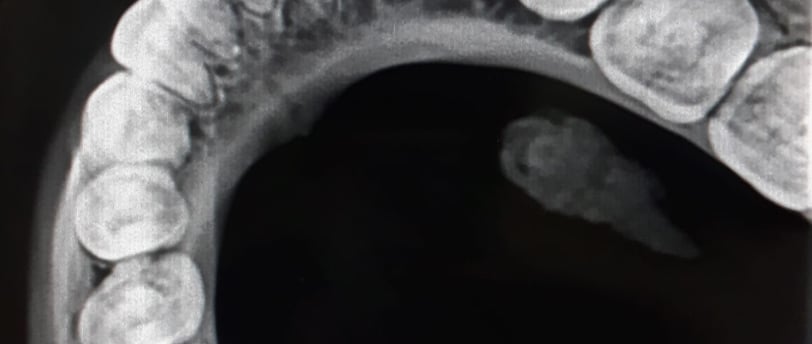

Radiografii occlusale

Radiografiile occlusale sunt utile pentru a evalua relația dintre dinți în timpul mușcării și pentru a depista probleme legate de alinierea dinților

Radiografiile occlusale sunt o formă specializată de imagistică dentară utilizată pentru a evalua relația dintre dinții superiori și cei inferiori în regiunea maxilară și mandibulară. Aceste radiografii sunt utile pentru a detecta probleme legate de alinierea și contactul dintre dinți, precum și pentru a identifica eventualele afecțiuni sau leziuni. În acest articol, vom explora radiografiile occlusale, tehnologia din spatele lor, beneficiile pe care le aduc și aplicațiile în îngrijirea dentară.

Radiografiile occlusale sunt proiectate să furnizeze imagini detaliate ale relației dintre dinții superiori și cei inferiori atunci când aceștia sunt în contact. Aceste radiografii se concentrează pe o zonă specifică și sunt utile pentru diagnosticarea și monitorizarea problemelor legate de occluzie, aliniere și contactul dintre dinți.